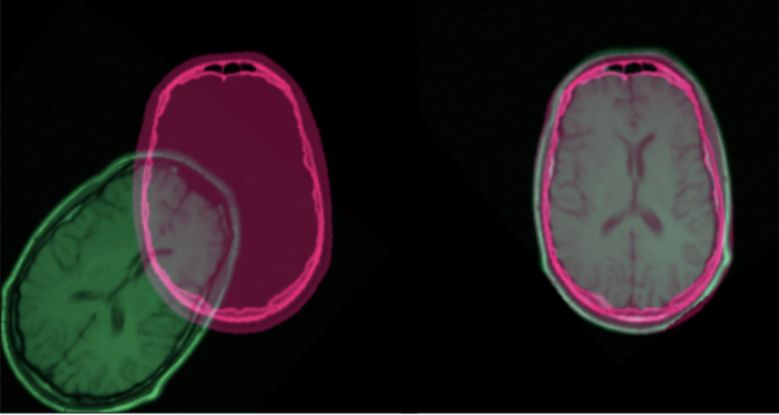

经过配准后的 CT 扫描和核磁共振图像